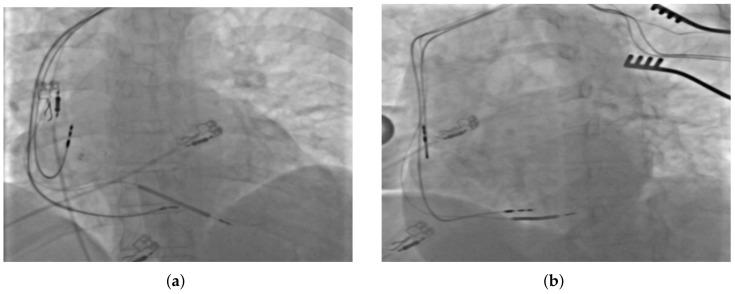

The results of clinical trials show that up to one-third of patients who are eligible for cardiac resynchronization therapy (CRT) do not benefit from biventricular pacing. The reasons vary, including technical problems related to left ventricle pacing lead placement in the appropriate branch of the coronary sinus. Herein, we present a case report of a patient with heart failure with reduced ejection fraction and left bundle branch block, in whom a poor coronary sinus bed made implantation of classic biventricular CRT impossible, but in whom, alternatively, rescue-performed left bundle branch area pacing allowed effective electrical and mechanical cardiac resynchronization. The report confirms that left bundle branch area pacing may be a rational alternative in such cases.